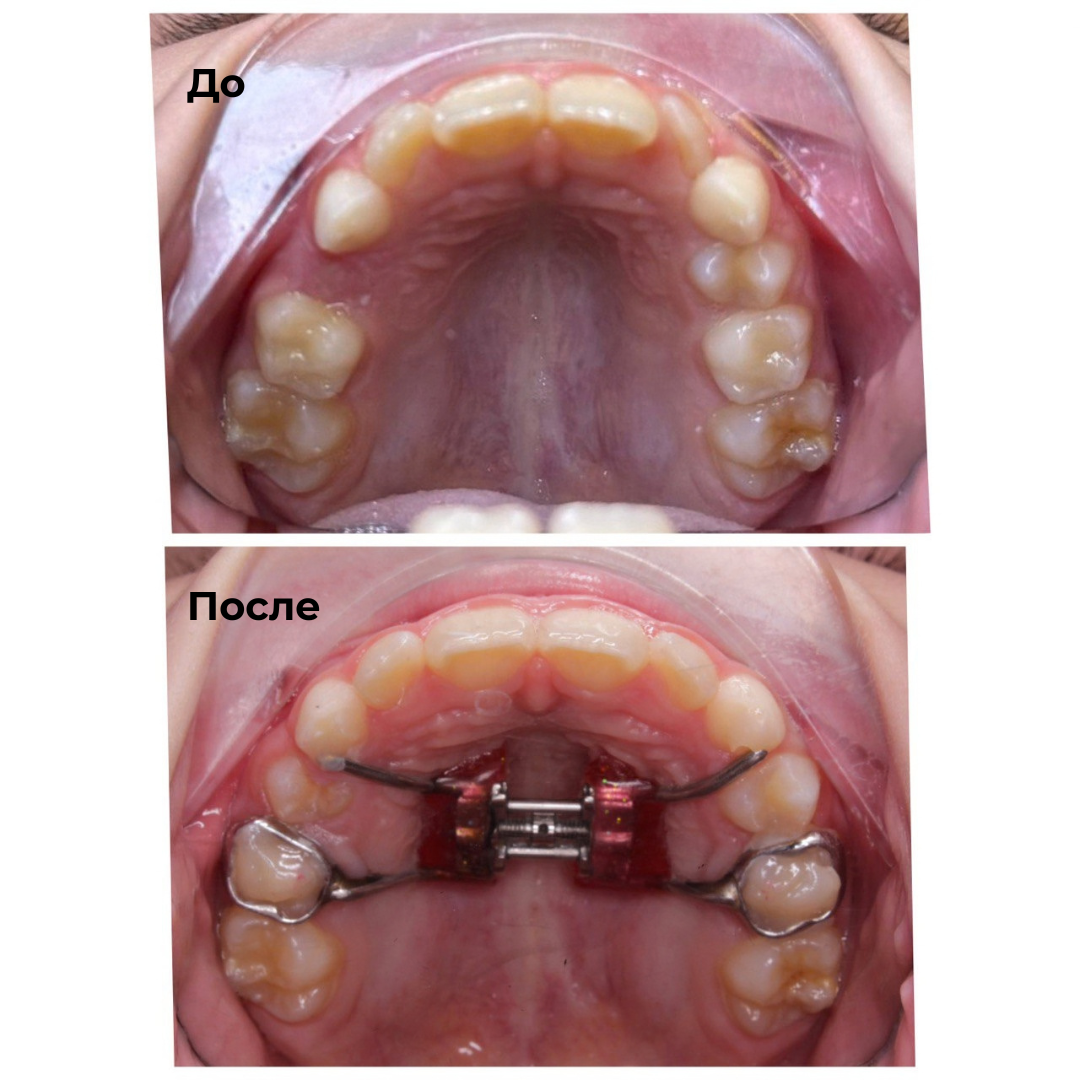

Такие результаты получают наши пациенты после лечения

Каждый случай - индивидуальный, но результат один: ровные зубы

Запишитесь на консультацию — подберём оптимальный план лечения под ваш случай.

✔ Работает со сложными случаями скученности и узкой челюсти у детей

✔ Работа с детьми: расширение челюсти и коррекция роста